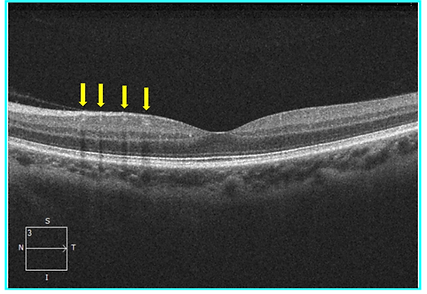

Patient Presentation: A 32-year-old male presents to the ophthalmology clinic for a routine follow-up assessment. His vision is 20/20 OD and 20/20 OS. His fundus examination was normal. The patient’s OCT macula is shown below.

Question: Which layer of the retina are the structures pointed by the yellow arrow located within?